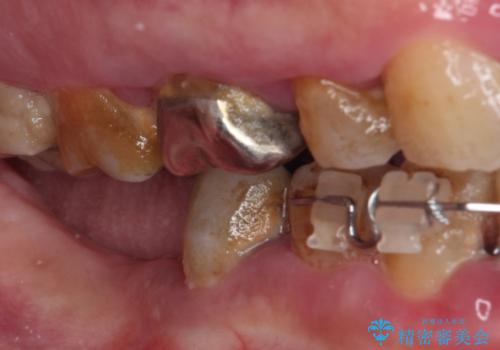

全体的に歯肉が腫れており、歯周病により抜歯をしなければならない歯がある状態でした。

矯正治療を仕上げ、必要に応じて歯周外科処置を行い、適宜インプラントを埋入しながら咬み合わせを回復させていくこととしました。

最終的に奥歯はオールセラミッククラウンによる補綴治療を行うこととしました。

治療前は磨き残しが多く見られ、全体的に歯肉が腫れている状態でしたが、抜歯の必要な歯を抜いたことで口腔内の環境が改善され、磨き残しも少なくなってきました。